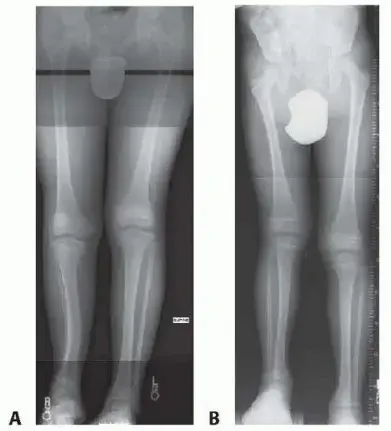

يُعد التشخيص الدقيق للسبب الكامن وراء فرق طول الأطراف أمراً بالغ الأهمية لتحديد خطة العلاج الأنسب. يعتمد الأستاذ الدكتور محمد هطيف على تقييم شامل يشمل التاريخ المرضي المفصل، الفحص السريري الدقيق، واستخدام أحدث تقنيات التصوير (مثل الأشعة السينية، الأشعة المقطعية، والرنين المغناطيسي، وقياس الطول بالأشعة السينية المسماة Scanogram) لتحديد السبب وحجم الفرق في الطول بدقة متناهية.

طرق التثبيت الخارجي (External Fixation):

- الوصف: يتم تثبيت جهاز معدني خارجي (مثل جهاز إليزاروف أو المثبتات الأحادية - Monorail fixators) على العظم بعد إجراء قطع جراحي (Osteotomy). يقوم المريض أو مقدم الرعاية بتعديل الجهاز يومياً ببطء شديد لفصل طرفي العظم، مما يحفز تكوين عظم جديد.

- جهاز إليزاروف (Ilizarov Method): نظام معقد من الحلقات والأسلاك والقضبان. يسمح بتطويل العظم وتصحيح التشوهات المعقدة في نفس الوقت.

- المثبتات الأحادية (Monorail Fixators): أبسط في التصميم، عبارة عن قضيب واحد يمتد على طول العظم.